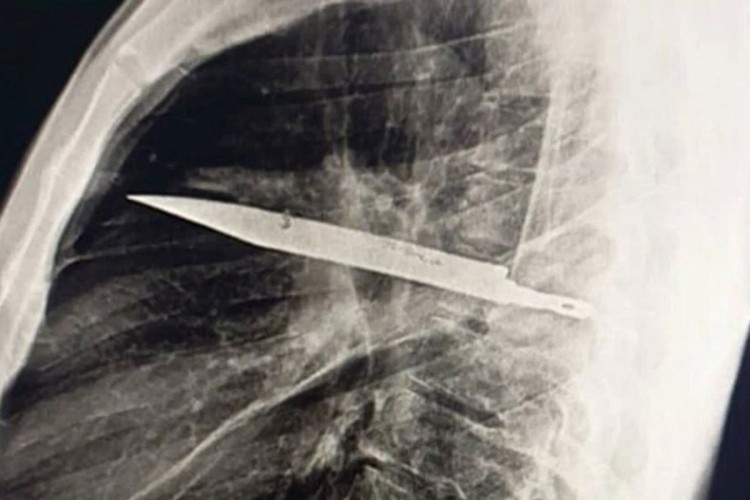

Nakon što je urađen rendgen, otkriven je “oštar metalni predmet”, a ljekari su shvatili da je u pitanju nož, okružen “gnojem i nekrotičnim tkivom”. Nož je u tijelo ušao kroz desno rame.

Hitno je preporučena operacija, tokom koje su ljekari uspjeli da izvade nož, a muškarac je proglašen dovoljno stabilnim da se već 10 dana kasnije vrati kući.

U izvještaju je ipak naglašeno koliko je imao sreće, jer je “iako se pacijent dobro oporavio nakon operacije, postojala značajna opasnost da zadržani nož dovede do smrtnog ishoda”.

Stručnjaci su objasnili da je razlog zašto je pacijent uspio da preživi toliko dugo sa nožem u grudima taj što je njegovo tijelo uspjelo da “obmota strano tijelo fibroznom kapsulom (čvrstim zaštitnim slojem tkiva), čime je ograničilo upalu i oštećenje tkiva”.